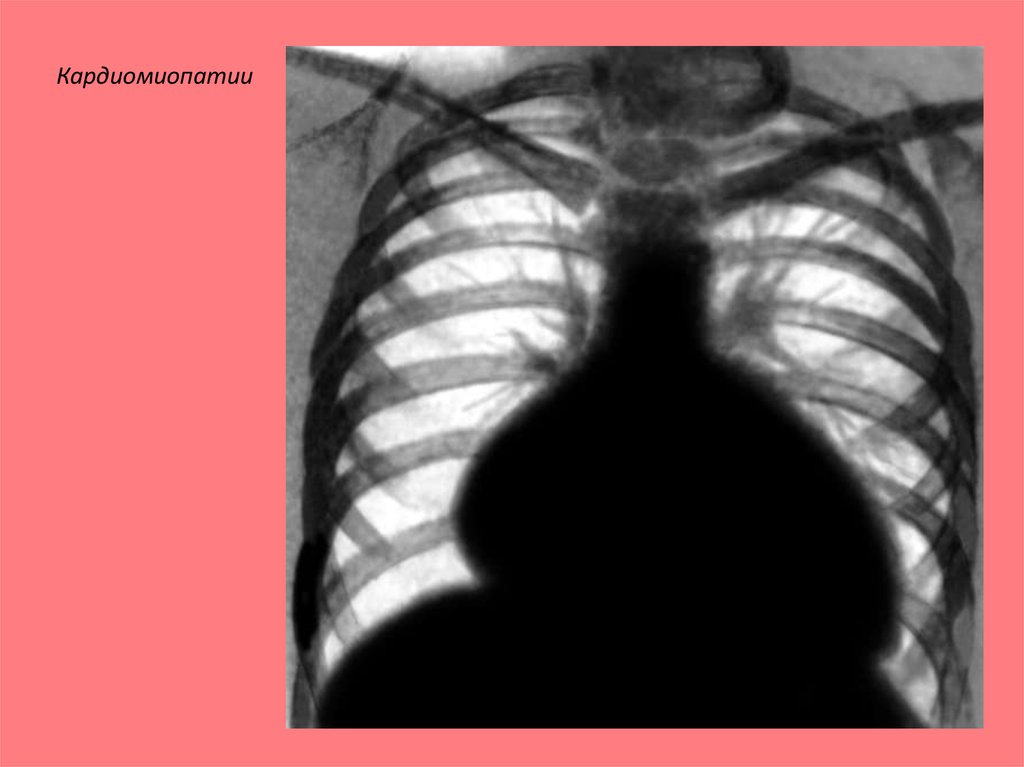

Кардиомиопатии